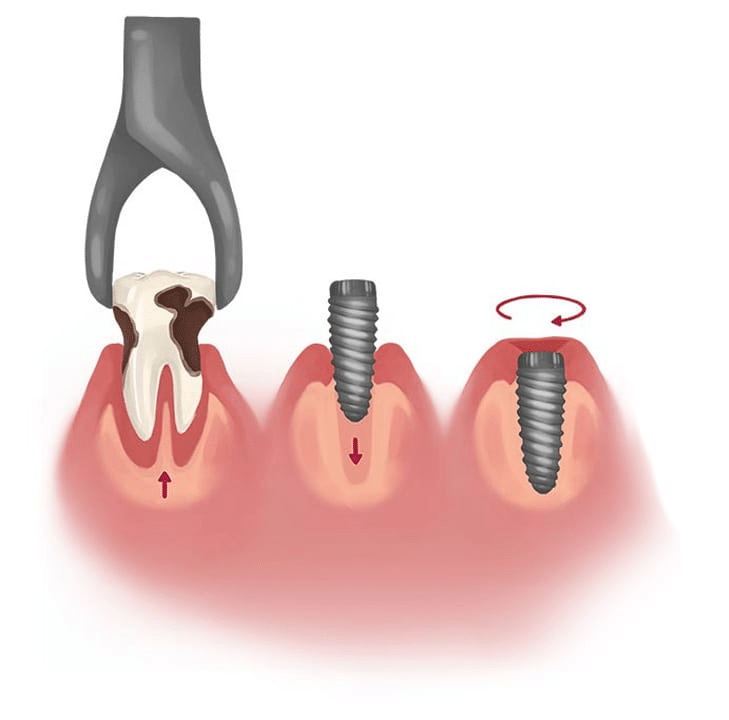

عملية زراعة الأسنان

- في يوم الجراحة، يتم خلع أسنانك وإعادة فحص العظام المحيطة بموقعها. إذا بدا أن العظام غير كافية، فيمكن إضافة الطعوم العظمية خلال هذه المرحلة.

- يتم وضع برغي من التيتانيوم مباشرة بعد إزالة الأسنان وإعداد العظام.

تركيب التاج الدائم

- بعد اكتمال الشفاء، يتم ربط الدعامة والتاج بعمود الزرع الخاص بك.